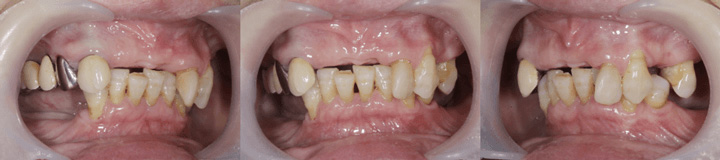

「初めて部分入れ歯を装着することになった」という方からの質問で、どういう構造なのか聞かれることがあります。

部分入れ歯は人工の歯だけだと落ちてくる、動くという現象が起こるため、上の写真のようにクラスプという細い金属を残っている歯にかけることになります。

こちらの写真は部分入れ歯を装着したところですが、クラスプ(残っている歯にかかっている細い金属)が確認できます。